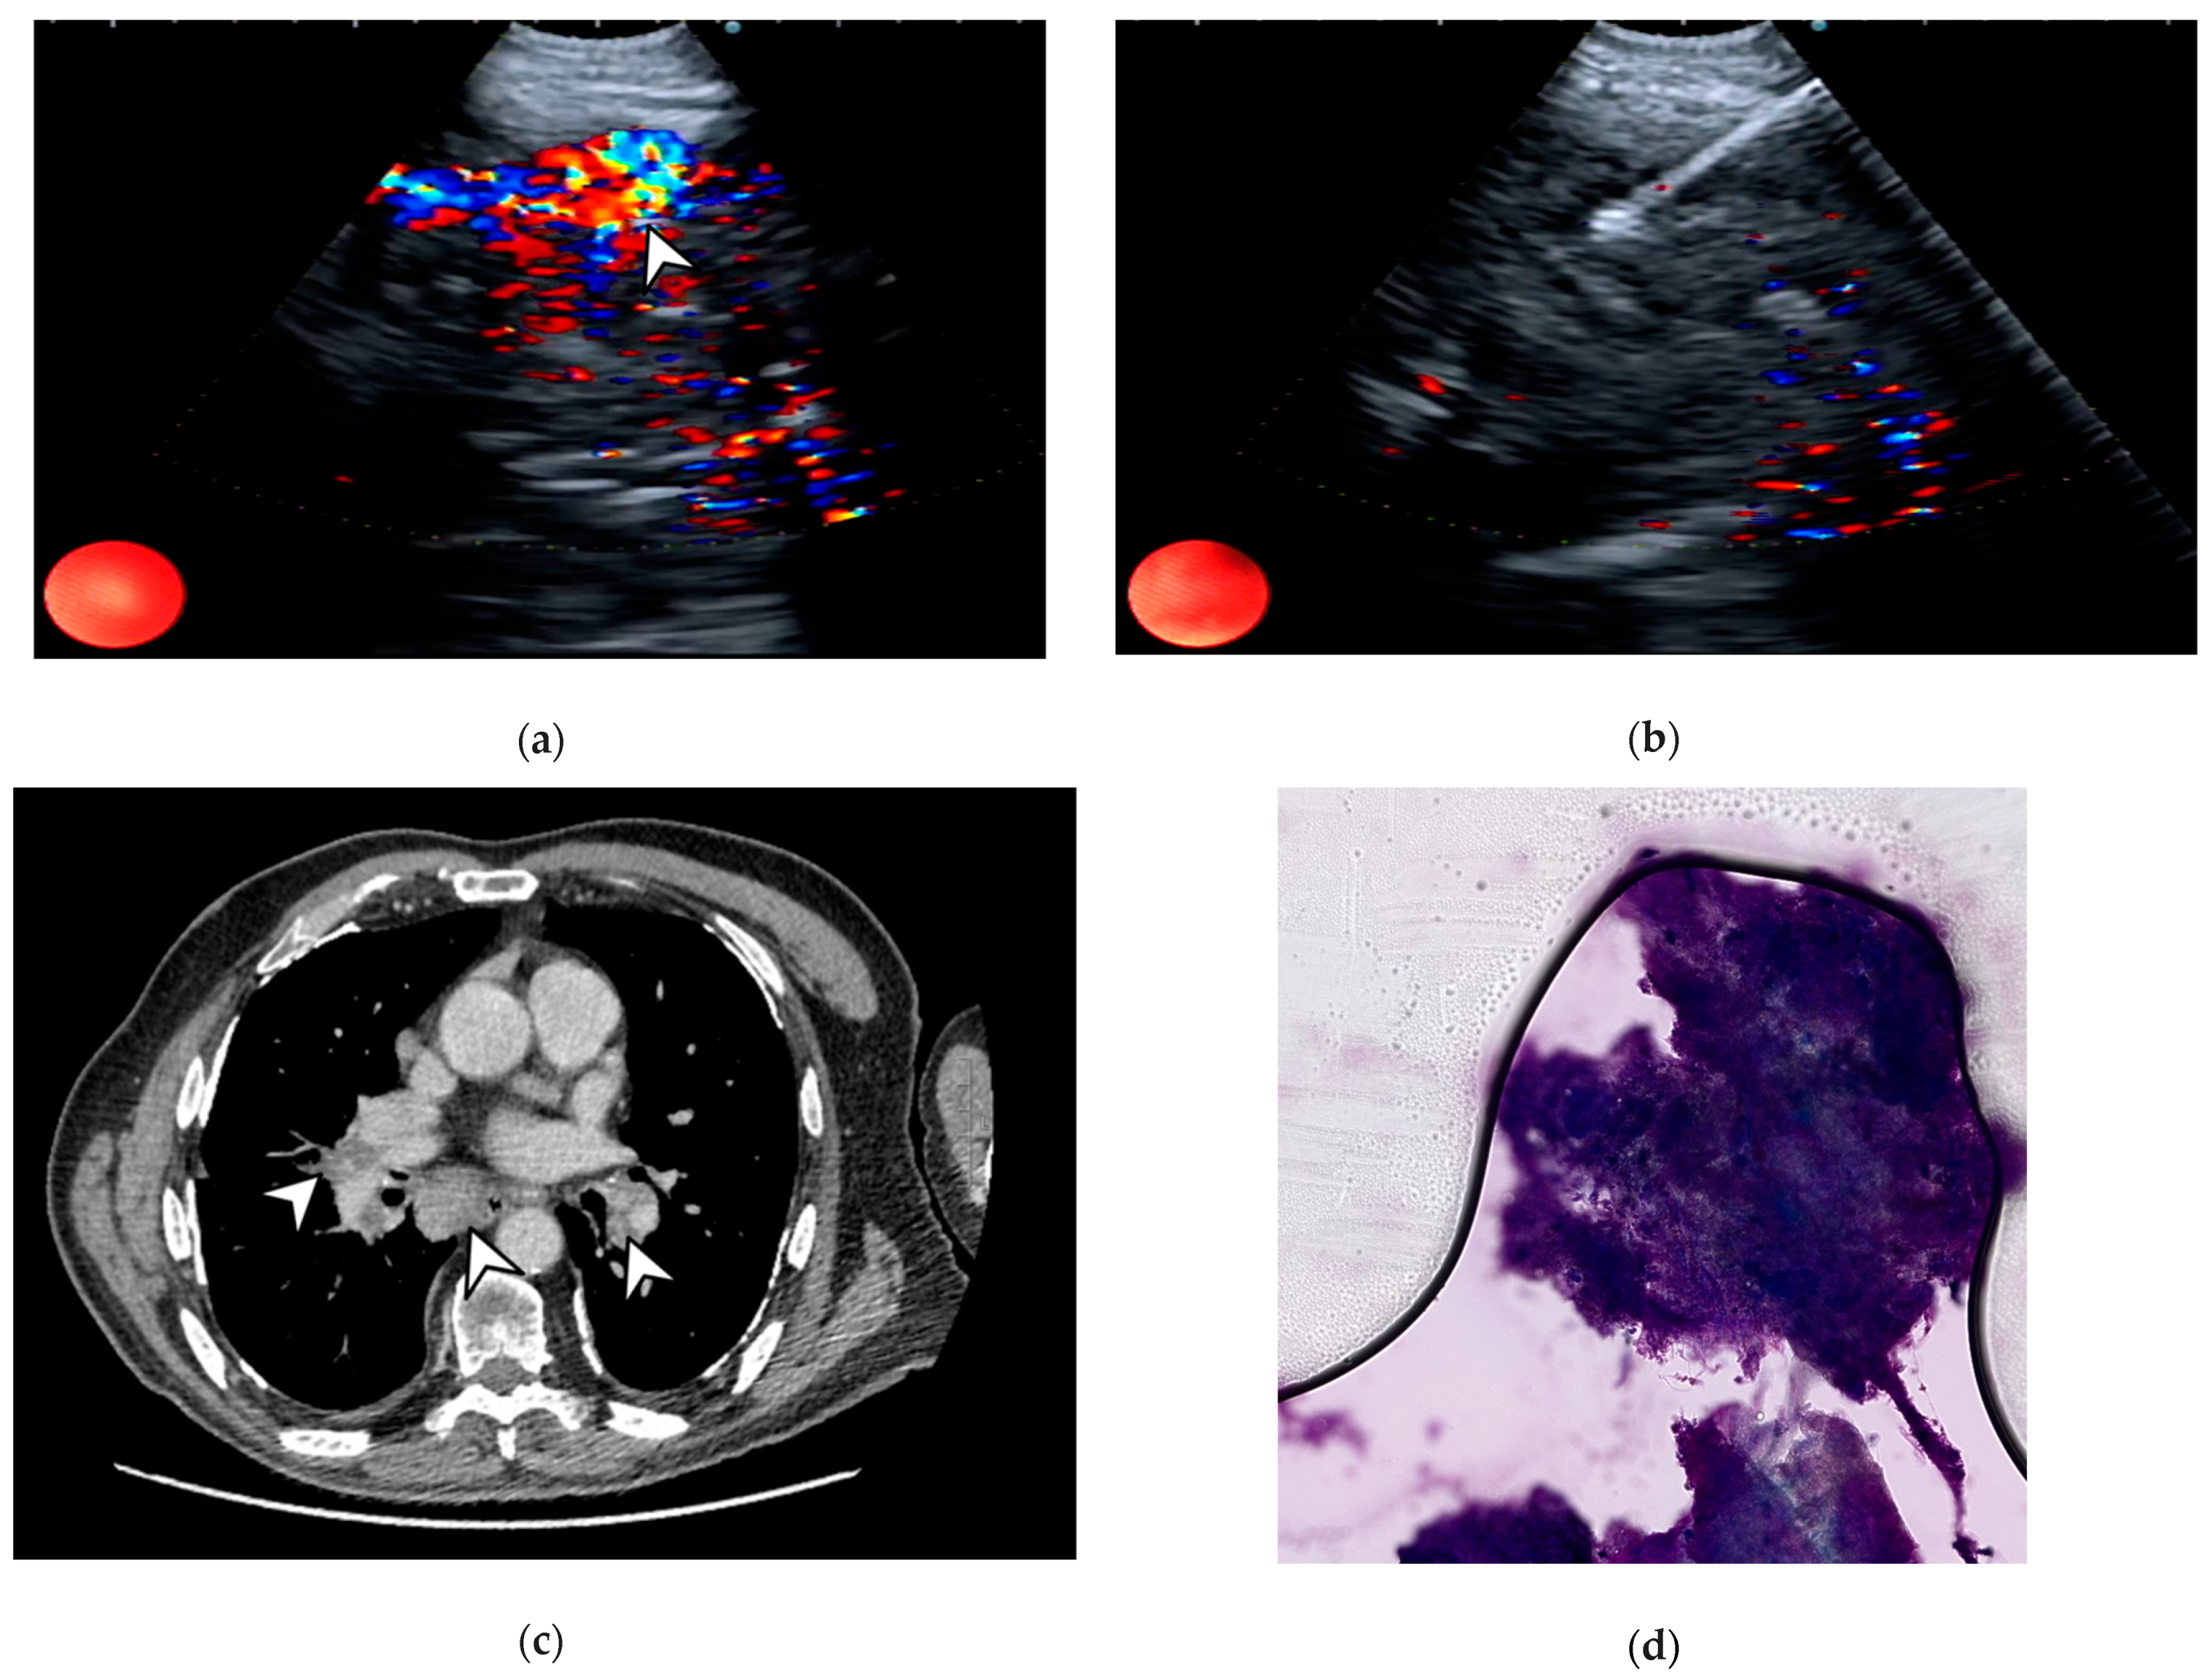

- Nakajima, T.; Anayama, T.; Shingyoji, M.; Kimura, H.; Yoshino, I.; Yasufuku, K. Vascular Image Patterns of Lymph Nodes for the Prediction of Metastatic Disease During EBUS-TBNA for Mediastinal Staging of Lung Cancer. J. Thorac. Oncol. 2012, 7, 1009–1014. [Google Scholar] [CrossRef] [PubMed]

- Nosotti, M.; Palleschi, A.; Tosi, D.; Mendogni, P.; Righi, I.; Carrinola, R.; Rosso, L. Color-Doppler Sonography Patterns in Endobronchial Ultrasound-Guided Transbronchial Needle Aspiration of Mediastinal Lymph-Nodes. J. Thorac. Dis. 2017, 9, S376–S380. [Google Scholar] [CrossRef] [PubMed][Green Version]